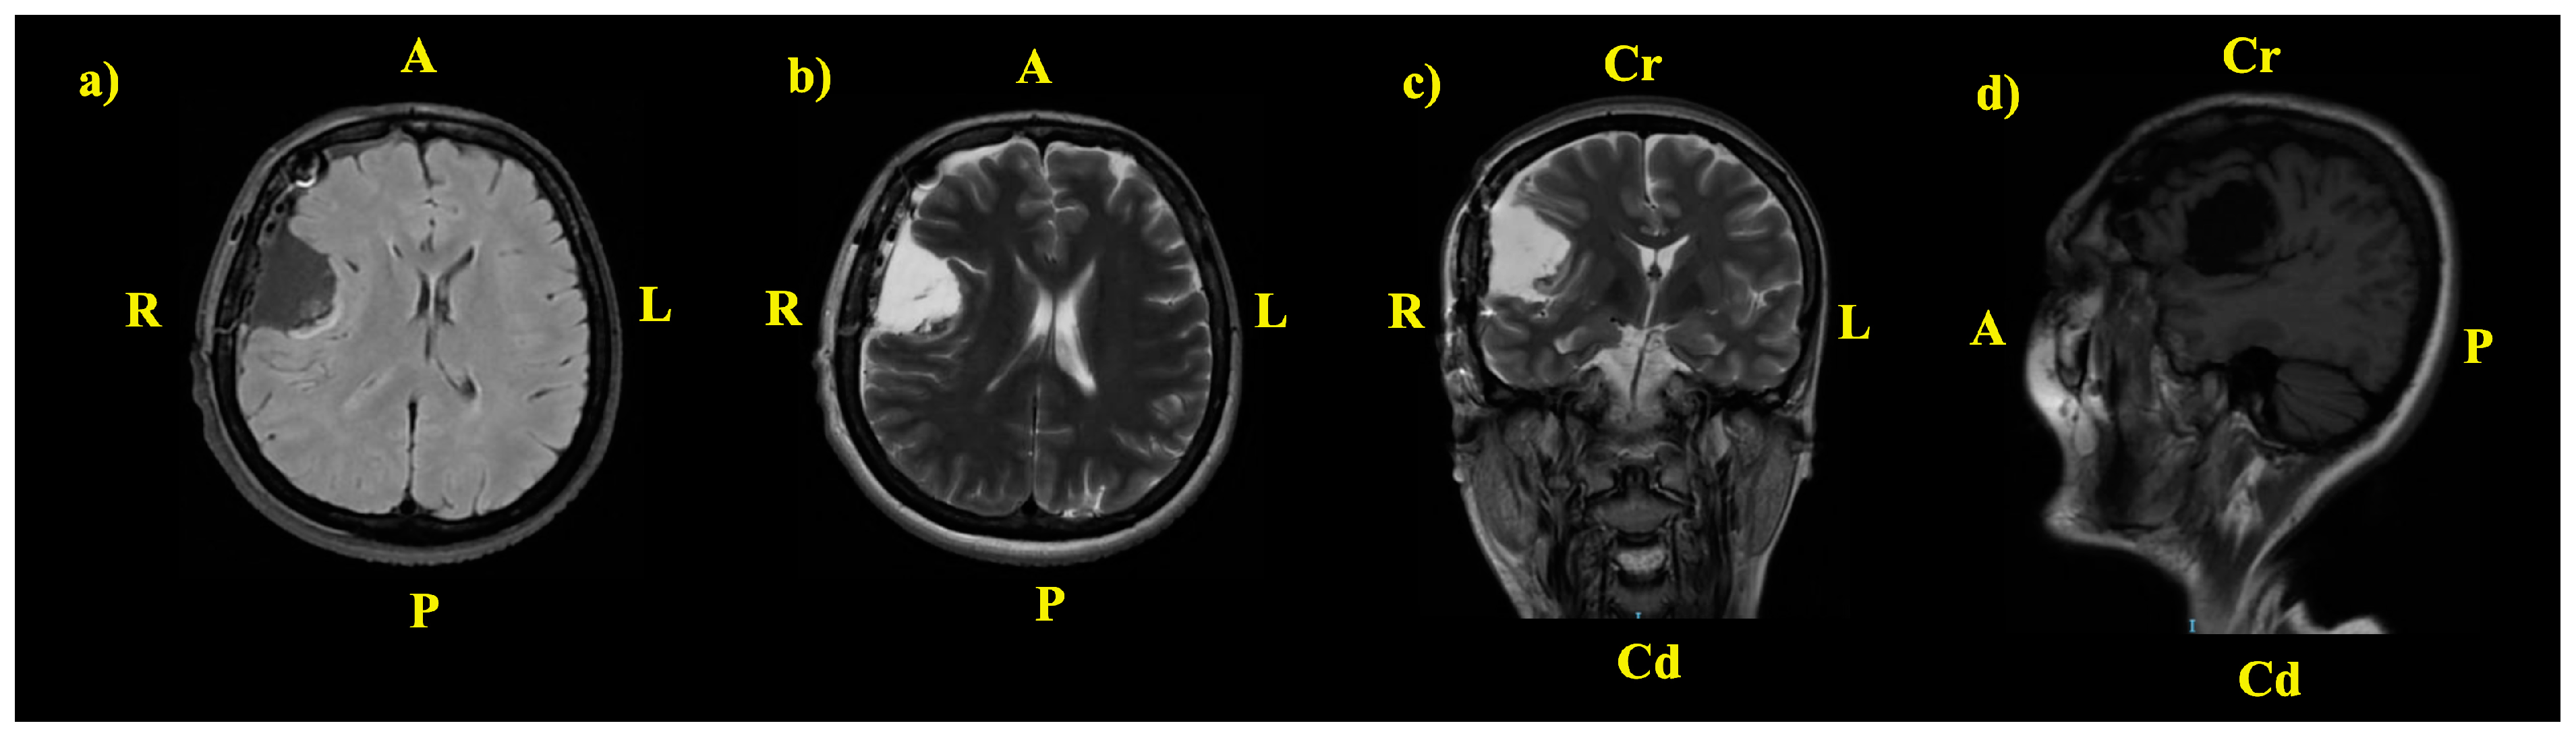

2. The Case: An Intriguing Case Unraveling Clinical and Paraclinical Complexities